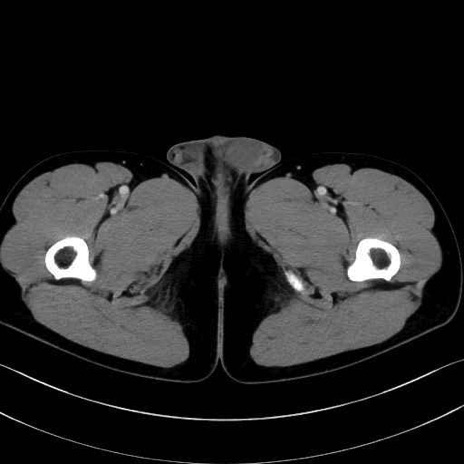

腸骨筋 (Iliacus)